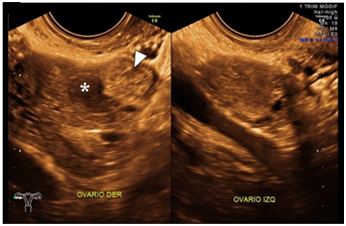

Female patient of 30 years of age, married, menarche at 10 years of age, 30x4 rhythm, with a history of dysmenorrhea, G1, P0, A0, C0. She went to a gynecologist-obstetrician for pregnancy control (7.5 SDG), referring to occasional colic and brown transvaginal waste without other aggregates. Within the analyzes of laboratory is found with Hb 12.5g / dl, leukocytes 8,000 uI, glucose 96mg / dL, β-HCG 2551mUI / mL, as well as general urinalysis (EGO) without alterations. On examination, transvaginal touch was performed, finding whitish leucorrhoea not fetid, so pelvic ultrasound (transabdominal) was requested, and qualitative control of β-HCG, and it was mentioned two days later. In this ultrasound uterus is reported without evidence of gestational sac (Figure 1) and second quantification of β-HCG of 2688mUI/mL. It is mentioned for the third time two days after showing ascending β-HCG quantification (2708mIU/mL), so it was decided to perform a new sonographic study by transvaginal route, confirming the presence of an empty uterine cavity (Figure 2); In addition, right ovary is observed with two nodules adjacent and inseparable from it; one of them with a hypoechoic aspect of 3 cm in diameter and the other of ecogenic appearance of 2.8 cm in diameter (Figure 3); later they are explored with Doppler mode, observing peripheral vascularity in the first (ring of fire sign) and scarce internal vascularity in the second considering itself what may correspond with body lute Y coat gestational disorganized respectively. Finally, indirect compression maneuvers are performed through the transducer, drawing attention to the "block" mobility of the right ovary with these nodules, which is why the probability of ectopic ovarian pregnancy is highly considered (Figure 4). It is sent with a treating doctor who decides to perform surgery (Figure 5); tissue samples are sent to study pathological he which reports "Findings compatible with pregnancy ectopic ovarian " (Figure 6).

Figure 3 Study of and ovarian sonography in which the right ovary is observed; as well as suggestive image of the luteous body (fleche tip) and adjacent echogenic nodule (*) from origin to determinal. Left ovum without apparent alterations.

Figure 4 Right ovary visualized via endovaginal where ovarian parenchyma with conserved vascularity is observed; ovidea and hypo echoic image suggestive of the luteum with peripheral vascularity (in ring). Finally, an adjacent echogenic nodule with internal vascularity is observed, with a low resistance resisence (not visualized in the image).